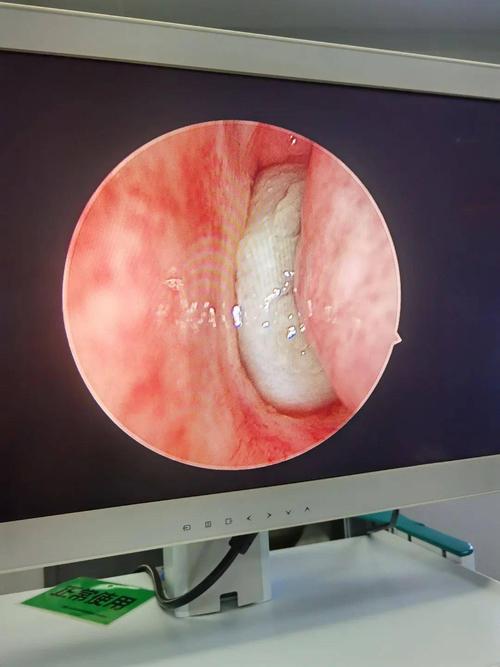

儿童鼻息肉图片库

儿童鼻息肉图片库,儿童正常鼻子内部图片

鼻息肉多发于中年以上,为何儿童也"中招"?

9岁"留守儿童"瘦骨嶙峋惹人疼,究其原因竟是鼻窦息肉致缺氧影响成长!

儿童鼻息肉可单发或多发,单侧或双侧,多数为多发性及双侧性.

儿童鼻息肉图片